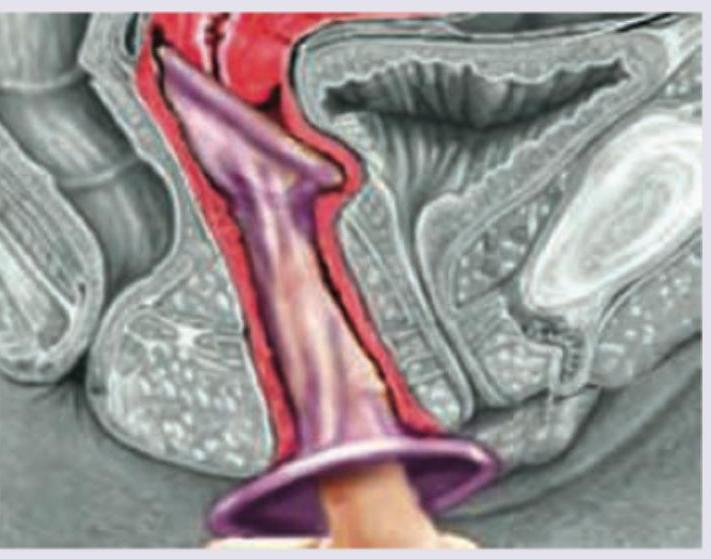

Which is not correct regarding the contraceptive method being used?

Explanation: ***Has lower failure rate than male condom*** - The **female condom** (as depicted in the image) generally has a **higher typical use failure rate** than the male condom based on most effectiveness studies. - While male condoms have an 18% typical use failure rate, female condoms have a typical use failure rate of about 21%. *Inner ring can irritate penis* - The flexible, **inner ring** of the female condom, which helps secure it in place against the cervix, can potentially cause **irritation to the penis** during intercourse due to friction. - This is a known concern for some users and their partners. *Made of polyurethane* - Female condoms are traditionally made of **polyurethane**, which is a synthetic rubber suitable for individuals with **latex allergies**, allowing for use with oil-based lubricants. - Newer versions may also be made of **nitrile** or other synthetic materials. *Pregnancy can occur if penis enters between the device and vagina* - If the **penis slips between the outer ring** of the female condom and the vaginal wall, sperm can be deposited directly into the vagina, leading to potential **pregnancy**. - Proper insertion and positioning are crucial to prevent this type of user error.